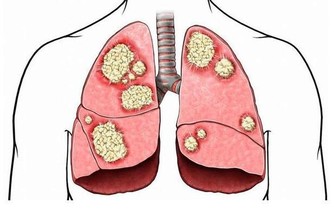

4、 胸痛

很多疾病可能引起胸口痛,最常見的有心臟問題、肺部問題、呼吸系統問題等,還有少部分是因為腹部或其他器官病變引起的。其中,急性心肌梗死、主動脈夾層動脈瘤、氣胸、肺栓塞、心包炎等高危疾病,都有可能在短時間內危及生命。若想預防胸痛,日常生活中我們應保持科學規律的飲食習慣,若出現胸痛可服用一些藥物幫助緩解不適,若疼痛持續時間長,需及時就醫。